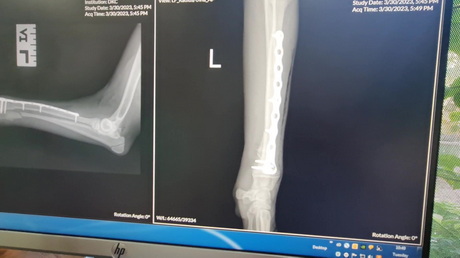

Radial Ulnar Fracture Repair in a Puppy

Play this video

08 Apr 2023

(Duration 08:28)